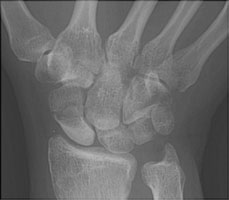

- Click on the image for a larger versionCPA radiograph of the wrist. Another patient shows the proximal pole to be dense and has undergone avascular necrosis. This is a known complication of waist fractures.